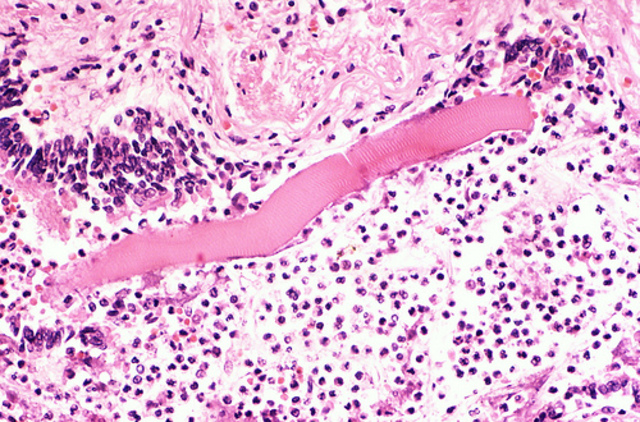

• Death

Death

Although I put up a great fight against pneumonia there was nothing more I could do. I was too ill to get the treatment I needed. I passed away during the night of December 8th. (cc) Pulmonary Pathology